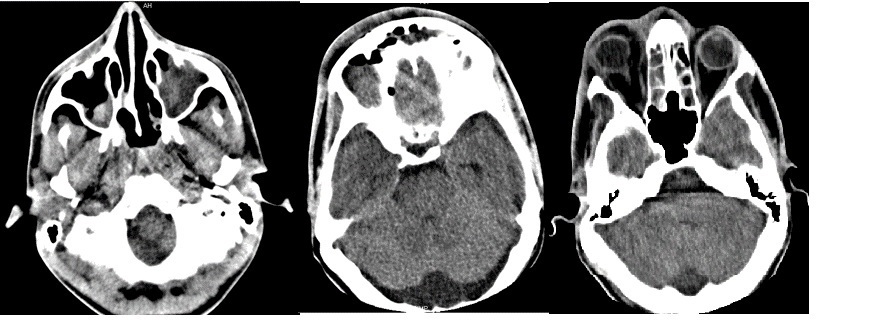

El estudio informó ausencia de línea de fractura; todas las cavidades que conforman los senos paranasales, exceptuando seno esfenoidal, se encontraban prácticamente ocupadas por material hiperdenso de aspecto inflamatorio, con formación de nivel en seno maxilar derecho y varios niveles en senos frontales, evidencias relacionadas con pansinusopatía. Se visualizó, además, proptosis del globo ocular de este lado, con aumento de la grasa alrededor del párpado y de la órbita, acompañado de colección con nivel hidroaéreo en la cara interna de la órbita, a nivel de los tejidos blandos subperiósticos, con erosión de la pared de las celdillas etmoidales contiguas y pared posterolateral derecha del seno frontal, presencia de gas periorbitario y perinasal anterior, con el aspecto de celulitis preseptal y orbitaria con absceso subperióstico y enfisema subcutáneo. A nivel de fosa posterior, fue visible un ensanchamiento del espacio subaracnoideo, con un IV ventrículo normal, por la presencia de una megacisterna magna (Fig. 1 y Fig. 2). En cortes a nivel de la región supratentorial se evidenció ligero borramiento de surcos y circunvoluciones por signos de hipertensión endocraneana (HTE). En la porción anterosuperior de la región frontal derecha se observó, además, imagen hiperdensa, de márgenes bien definidos, convexa hacia el parénquima cerebral, con grosor máximo de 23 mm, sin edema perilesional, la cual provocaba efecto de masa con compresión del asta frontal del sistema ventricular ipsilateral y desplazamiento 9 mm de estructuras de la línea media, por colección epidural (Fig. 3).

Todos estos hallazgos tomográficos condujeron a la siguiente impresión diagnóstica: Colección epidural, signos de HTE, celulitis orbitaria y absceso subperióstico secundarios a pansinusopatía complicada; megacisterna magna. El paciente fue intervenido quirúrgicamente, con evolución clínica favorable, a pesar de la pérdida de visión del ojo afectado.